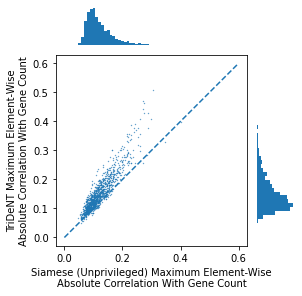

To assess the level of information shared between the transcriptomic results and the representations of the H&E patches, we investigate the cross-correlation between elements of the representations and the gene counts for each matching patch. We calculate the cross-correlation across the validation set between each element in the representations and the count for each gene, and for each gene take the correlation of the corresponding element with the maximum correlation or minimum anti-correlation, whichever has the greater absolute value. This maximum/minimum is chosen because the vast majority of elements will not correlate with any given gene, and the absolute value is taken because the sign of the element is arbitrary, so correlation and anti-correlation are equivalent. We use the absolute value of the correlation for the element selected for each gene, and use these to generate the histograms in Figure 3(a). It is clear that privileged training obtains representations which are far more correlated to the gene counts than unprivileged training, with minimal differences in the correlations between TriDeNT ♆ and Siamese approaches. This implies that the models have learned equivalently informative representations about the coarse-grained features of the genes. Figure 3(c) demonstrates that the correlation strength is significantly greater for TriDeNT ♆ compared to an unprivileged Siamese model, and Figures S3 and S4 show the relationships between the gene correlations of representations from TriDeNT ♆, Siamese methods, and supervised learning. Figures S5 and S6 show the geneset enrichment for each method, demonstrating that TriDeNT ♆ captures more meaninful interrelationships that are more informative about the relationship between tissue morphology and gene expression than unsupervised Siamese models. This is especially important for scientific discovery, as these analyses are used to generate hypotheses for further research. Figure S7 shows UMAP projections of the representation space coloured by genotype and gene, to illustrate that TriDeNT ♆ identifies distinct morphological clusters which are not found by unprivileged Siamese models. Figure 3(a) also shows that the findings are robust to human and mouse datasets, indicating the generality of the method.